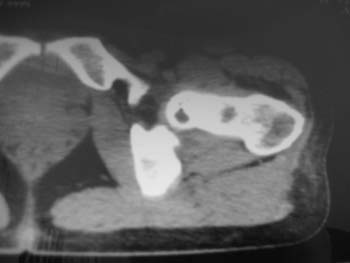

以下是引用358450m在2008-8-12 12:12:00的发言:[br]骨囊肿

以下是引用yangyudong333在2008-8-12 14:30:00的发言:[br]考虑退京变所致关节面下骨质囊变

以下是引用随光逐影在2008-8-12 20:40:00的发言:[br]考虑邻关节骨囊肿或骨内腱鞘囊肿。